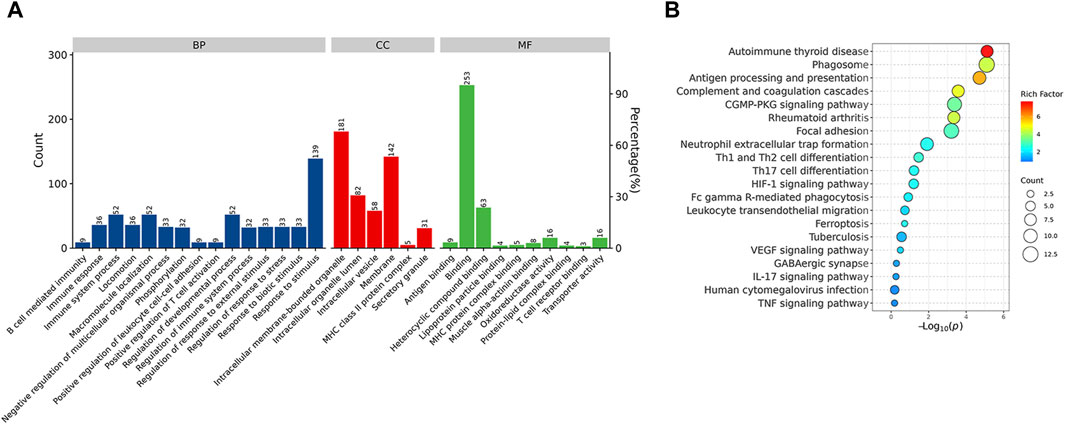

GO and kyoto encyclopedia of genes and genomes enrichment analysis for DEPsFunctional enrichment analysis demonstrated that the DEPs were primarily involved in the immune system process and response to stimulus, which might be associated with the Rifampicin-resistant mechanism of spinal tuberculosis induced by the immune system process (Figure 5A). Notably, five proteins annotated with the term human leukocyte antigen, A Chain ((HLA-A), human leukocyte antigen, C Chain ((HLA-C), HLA Class II Histocompatibility Antigen, DRB1 Beta Chain (HLA-DRB1), metalloproteinase 9 (MMP9) and Phospholipase C-like 1 (PLCL1) were significantly changed compared with NDSTB (Supplementary Table S4). KEGG pathway analysis demonstrated that DEPs were mainly associated with “Antigen processing and presentation” and “Phagosome” (Figure 5B). These findings contribute novel perspectives to our understanding of the etiology and comorbidities associated with drug-resistant spinal tuberculosis.

Figure 5. (A) BP, the cellular component category (CC), the molecular function category (MF) phantom enrich mentanalysis of DEPs. The left vertical coordinate is count (number of differential proteins annotated to the term), and the right vertical coordinate is percentage (number of differential proteins annotated to the term/total number of differential proteins with GO annotations). (B) KEGG enrichment pathway analysis of DEPs. The abscissa represents the negative logarithmic transformation of the Enrichment factor, and the ordinate represented the specific path. The column color indicates -log10 (p-value). Specific counts and p-values are presented on the right side of the column. KEGG, Kyoto Protocol Encyclopedia of Genes and Genomes; DEPs, differentially expressed proteins.